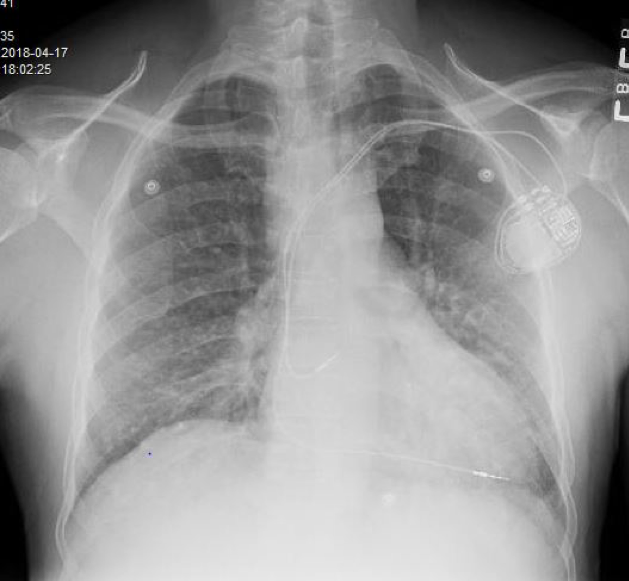

The chest radiographs showed extensive mediastinal and bilateral lymphadenopathy (Figure 1).

Figure 1.The CT scan of the abdomen and pelvis (Figures 2 and 3) showed an enlarged liver almost completely replaced by multiple low-attenuation lesions, none larger than 20 to 30 mm. The spleen was also enlarged, with multiple lesions measuring up to 20 mm. Extensive enlarged upper abdominal, periportal, and retroperitoneal lymph nodes were noted. These radiographic findings were suggestive of sarcoidosis or lymphoma.